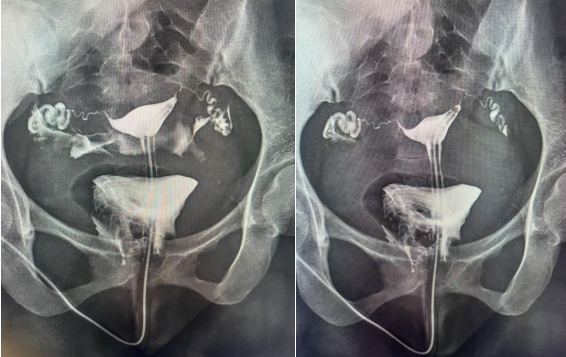

子宫输卵管造影是通过导管经阴道、子宫颈向宫腔及输卵管内注入造影剂,利用X线诊断仪透视并拍片,根据造影剂在子宫、输卵管及盆腔内的显影情况,来了解和判断子宫腔形态,是否畸形、粘连,输卵管是否通畅,以及输卵管阻塞的部位。常用于不孕症、输卵管再通、子宫畸形等疾病的诊治。如